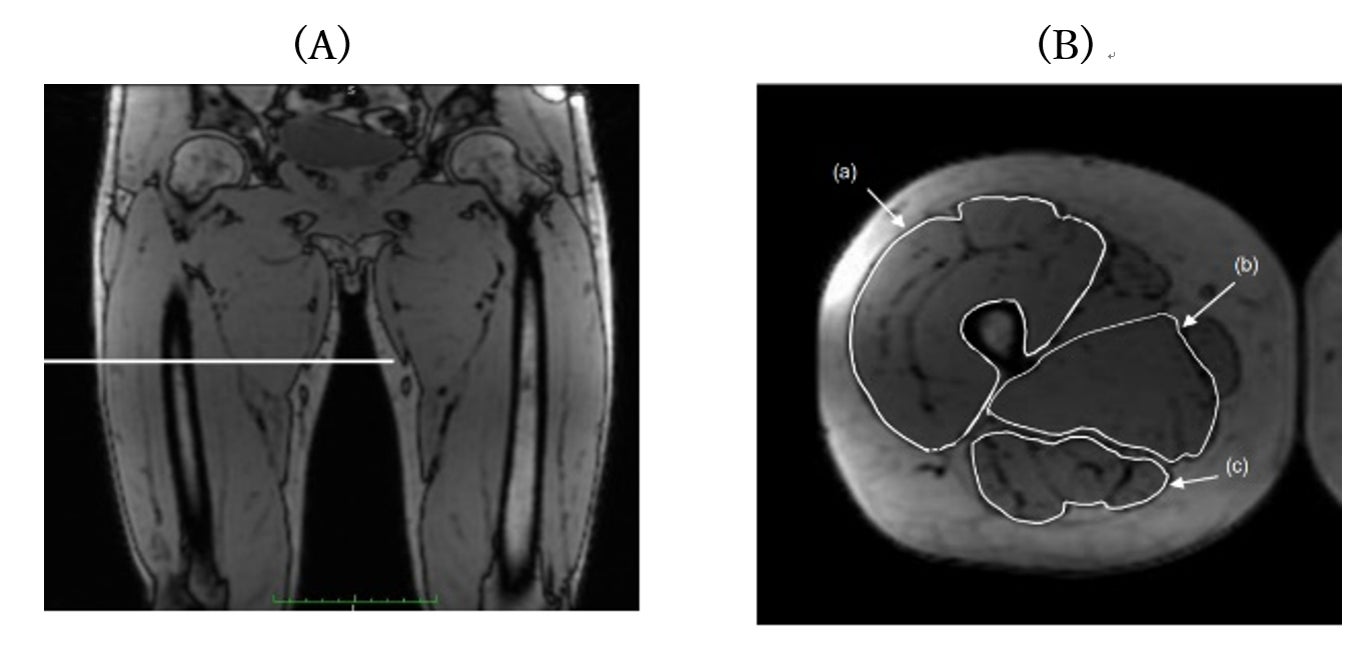

■磁気共鳴画像(MRI)(図1)

(A)大腿部の両側冠状断磁気共鳴画像。白線は右大腿部の断面撮影ポイントを示しています。

(B)右大腿部の断面画像上における筋群の分割。(a) (b) (c)はそれぞれ大腿四頭筋、内転筋、ハムストリングスを示しています。